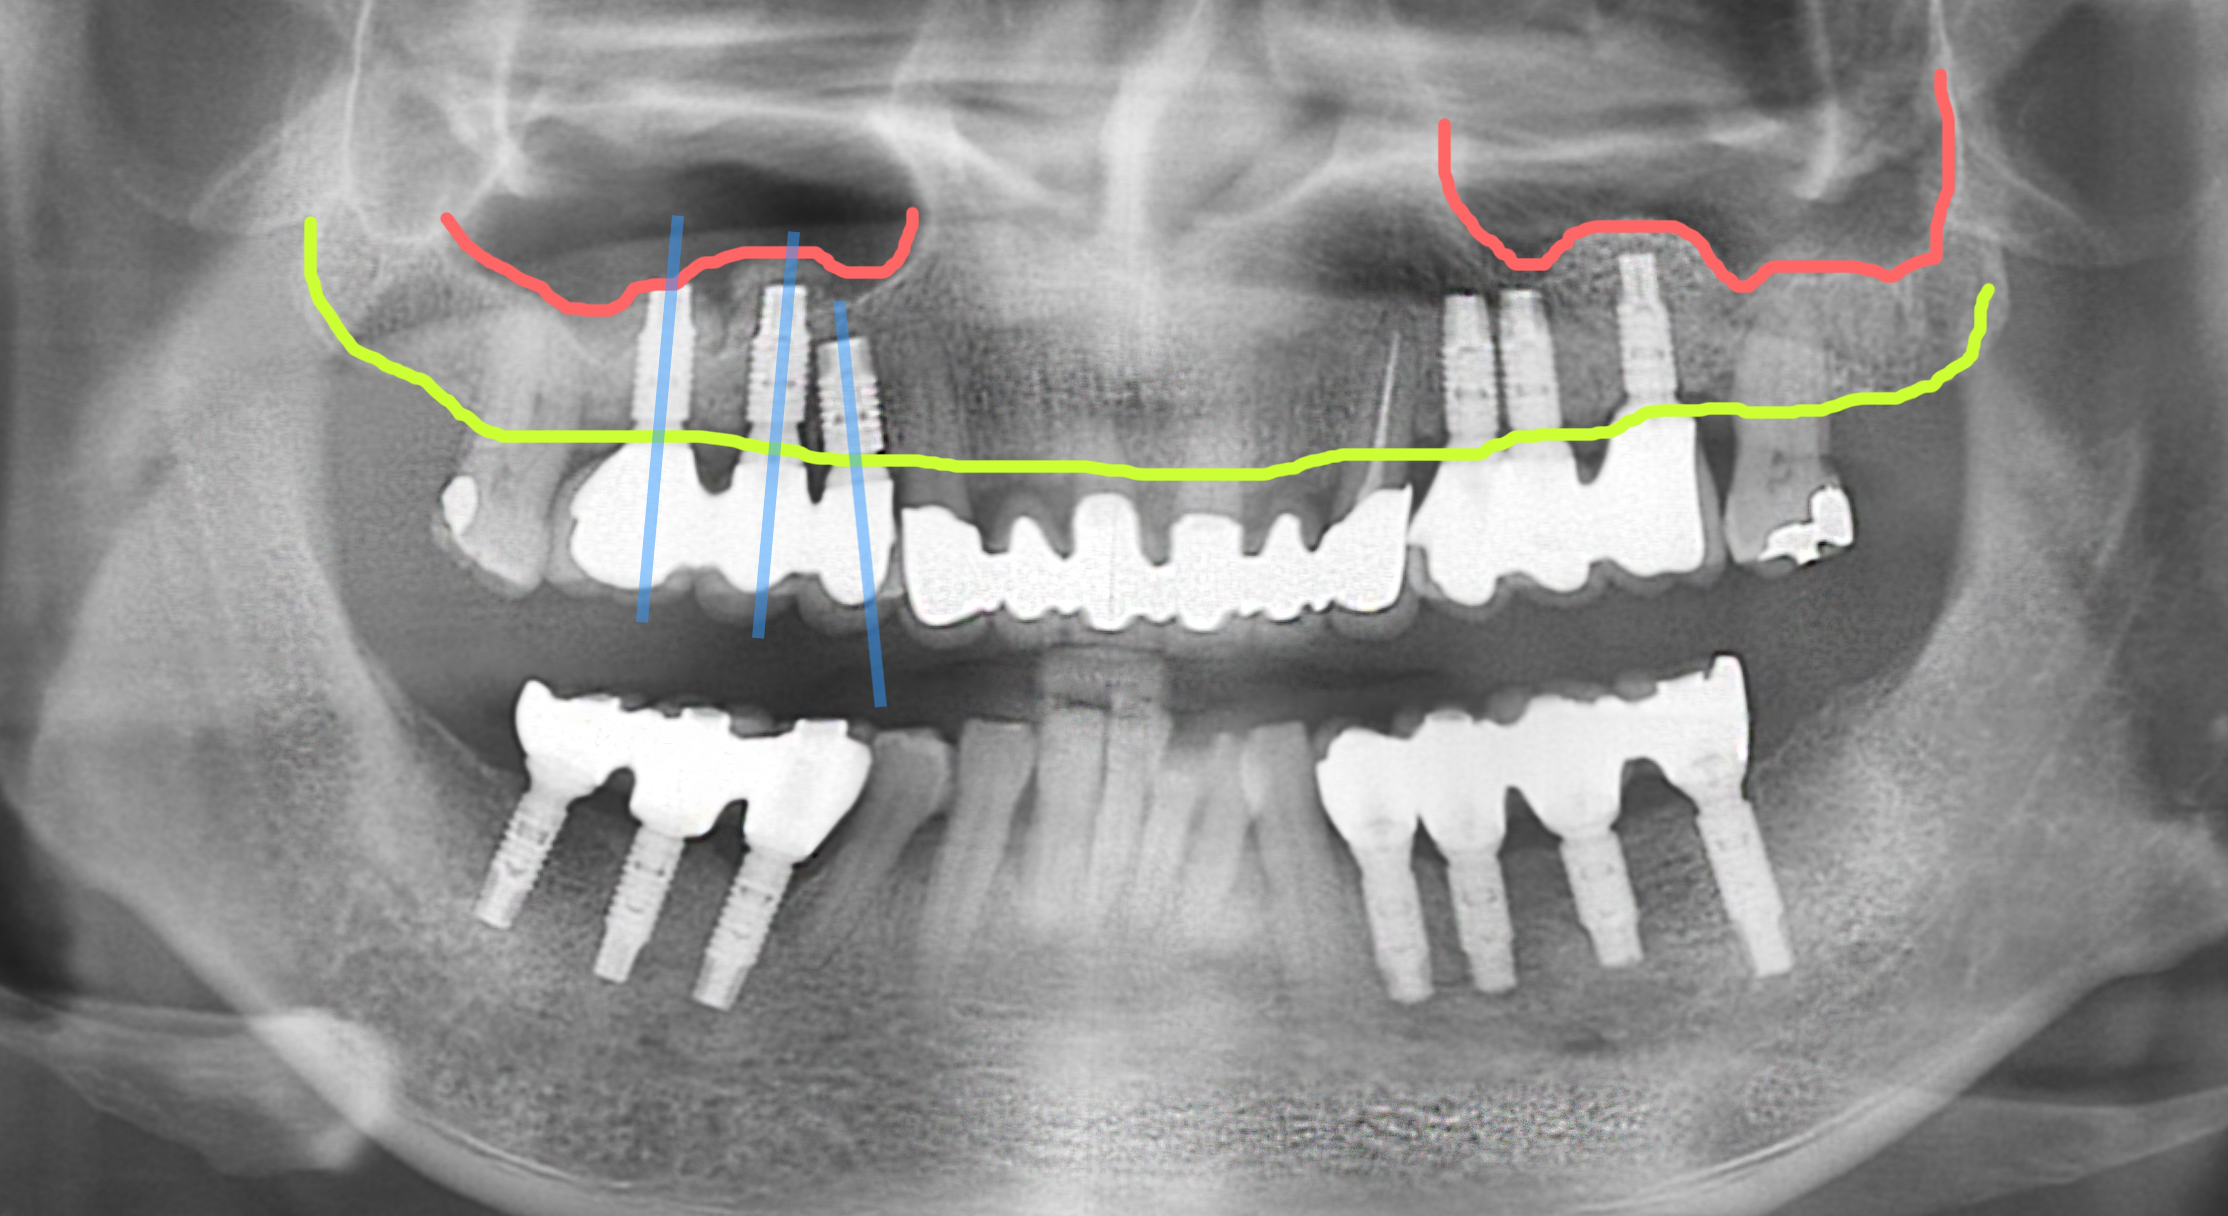

무치악 임플란트는 구강 전체에 대한 정확한 이해가 필요한 치료입니다.

치아가 전혀 없거나 모든 치아를 발치하게 되었을 경우 모든 치아를

임플란트로 대체해야 한다는 고난이도의 시술입니다.

단순히 많은 수의 임플란트를 식립하는 것이 아니라, 환자분들께 씹는 즐거움을

되찾아드리기 위하여 치과에서는 위, 아래 치아의 정확한 교합

치아와 잇몸과의 조화로운 비율을 고려한 미소 디자인, 마지막으로 수술 부담을

줄이기 위해 환자에게 맞춘 최적의 임플란트를 설계하여 치료합니다.

무치악 임플란트 시술은 늘어난 임플란트 갯수만큼 어려운 시술이며

반드시 풍부한 임상경험이 뒷받침 되어야 합니다.